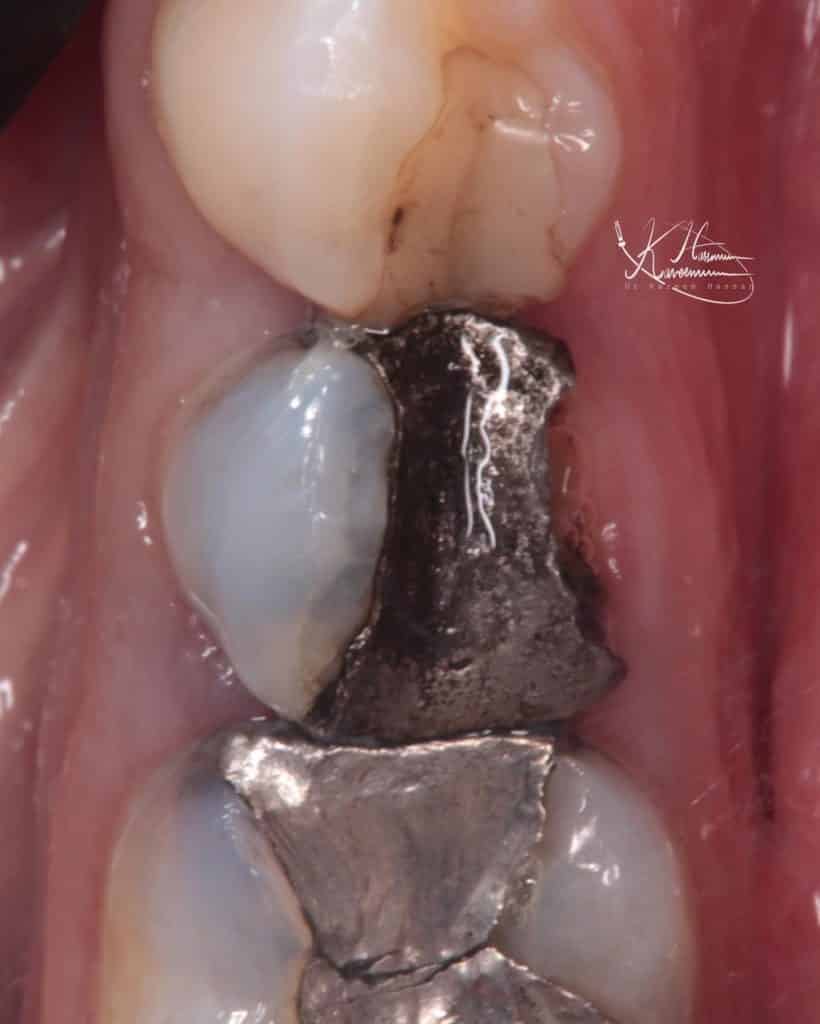

Patient attended my clinic suffer from fracture old restoration and want to save the remaining structure

After good clinical and radiographic examination,

Fortunately, The examination reveal that the tooth still vital

Initial situation

Buccal view